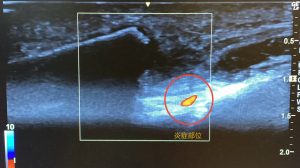

右鎖骨部骨折部エコー画像

右鎖骨部骨折部エコー画像(炎症反応あり)